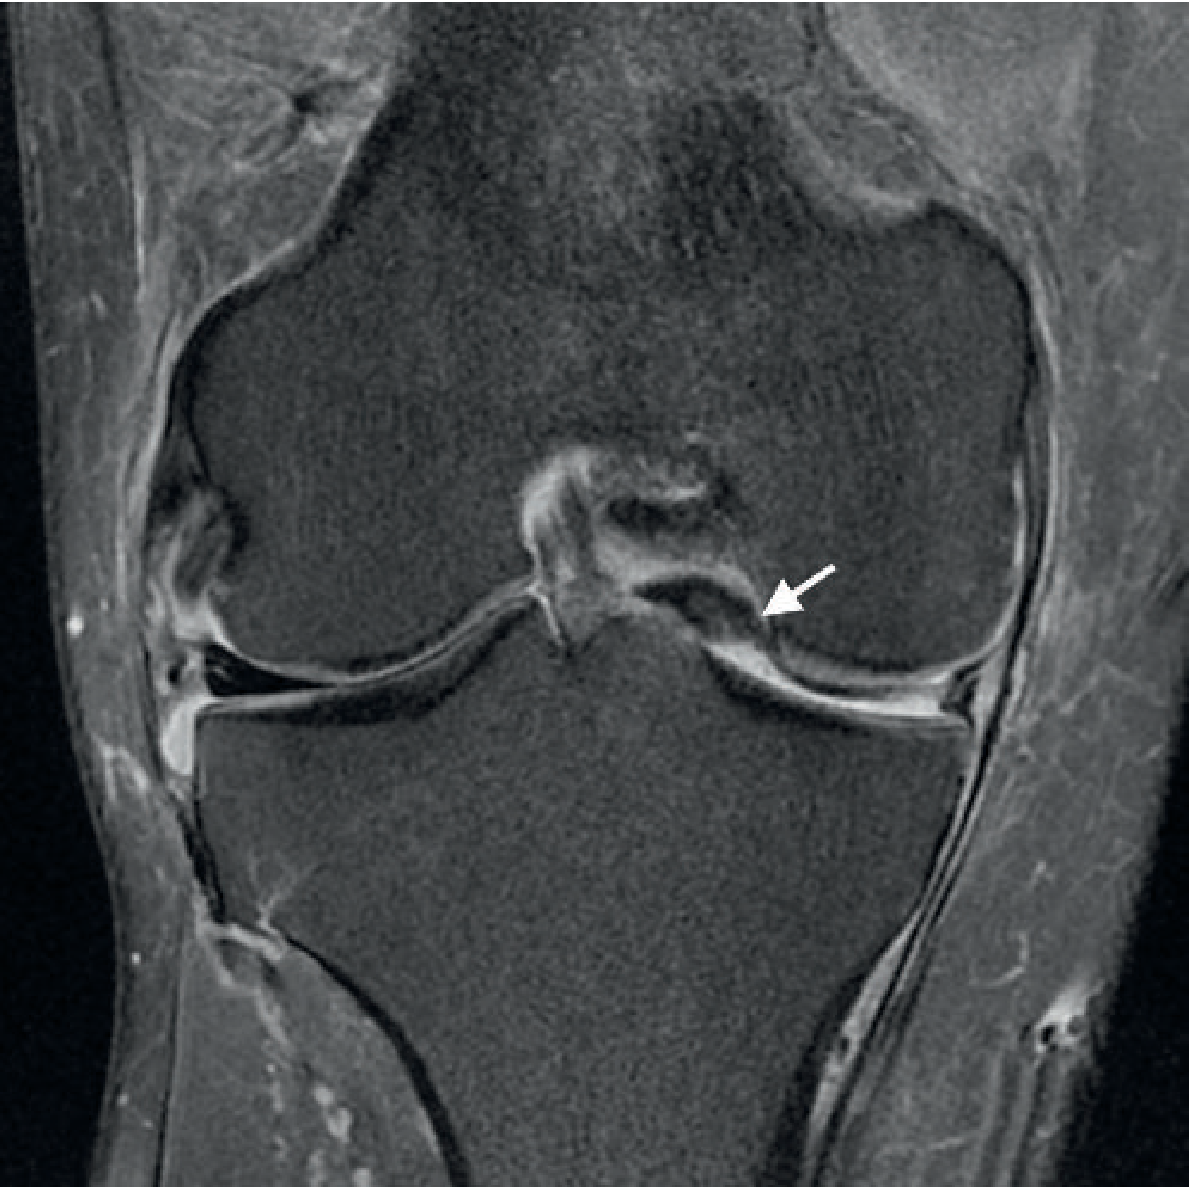

MRI appearance:

• Sagittal: "Ghost sign" — absent posterior horn signal where root should anchor

• Coronal + axial: focal high-signal gap at root attachment

• Key secondary finding: meniscal extrusion >3 mm beyond the tibial margin (loss of hoop stress causes the meniscus to be extruded radially)

• Medial root tears: often associated with subchondral marrow edema and cartilage loss

Coronal (A), axial (B), and coronal measurement (C) MRI demonstrating medial meniscal posterior root tear with 3.15 mm meniscal extrusion

Medial meniscal posterior root tear with measurable meniscal extrusion (PMC)